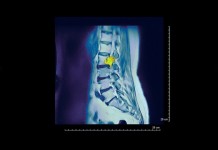

Опухоли спинного мозга

Опухоли спинного мозга – новообразования в спинном мозге, доброкачественные или злокачественные по своей природе. Опухоли спинного мозга могут быть как первичными (образуются из клеток спинного мозга),...